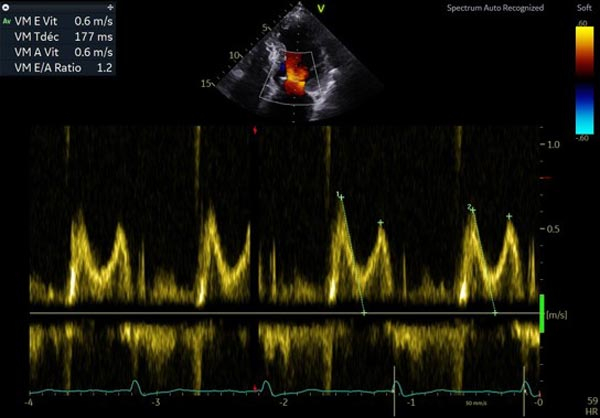

- PRVG normales, profil mitral en trouble de relaxation onde E 0.4m/s

Figure 3 : profil mitral normal